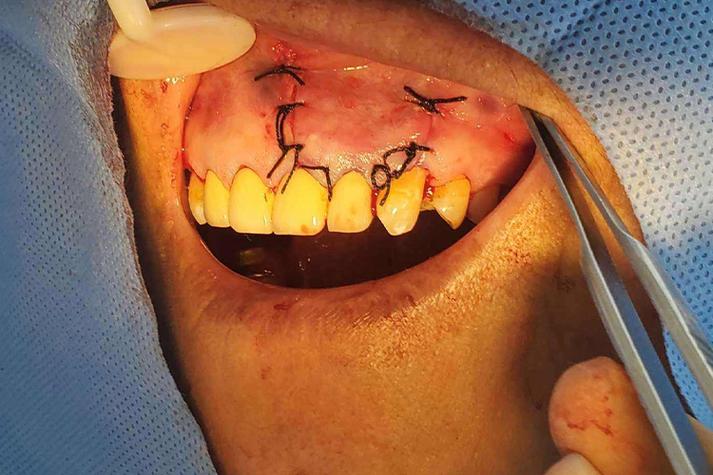

种牙(种植牙)手术后,缝线(缝合线)所在的部位是手术切口的位置,是整个种植体植入的关键区域,术后对这个部位的护理至关重要,直接关系到手术的成功和愈合速度,以下是关于种牙后缝线部位的重要信息和护理要点:

- 作用: 缝线的主要目的是将手术切口处的牙龈组织精确地缝合在一起,覆盖住种植体(骨结合部分),促进伤口愈合,减少感染风险,并形成良好的“袖口”(牙龈袖口),为未来牙冠提供健康的软组织基础。

(图片来源网络,侵删)